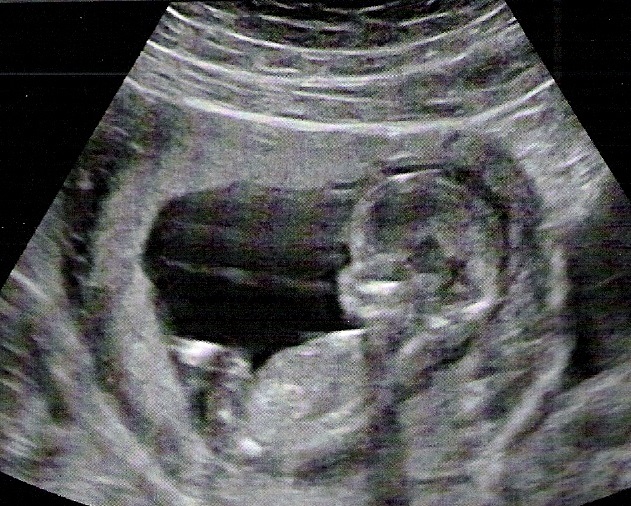

Échographie

L’échographie est une technique médicale qui permet d’obtenir des images grâce aux ultrasons qui sont inoffensifs et indolores (par contre, ce qui peut être douloureux c’est l’appui du praticien suivant l’angle de vue qu’il essaiera d’avoir), le tout afin de visualiser le fœtus. Cet examen donne des informations comme le nombre d’embryons, l’état de santé du futur bébé :

• sa vitalité : activité cardiaque et ses mouvements,

• sa morphologie : exploration des organes,

• ses mensurations : périmètre de la tête, périmètre abdominal, longueur du fémur,… afin de définir le début de grossesse et pour suivre sa croissance.

On en recommande 3 lors d’une grossesse, une à chaque trimestre. Ci-dessous quelques images d’échographie, tout d’abord le battement de son cœur et l’analyse du cœur ainsi que quelques prises de mesures qui aideront à définir la date prévue d’accouchement afin de faire la déclaration de grossesse : Image en 3D de la tête du bébé, lors de l’échographie du 2ème trimestre : echo3D_internet